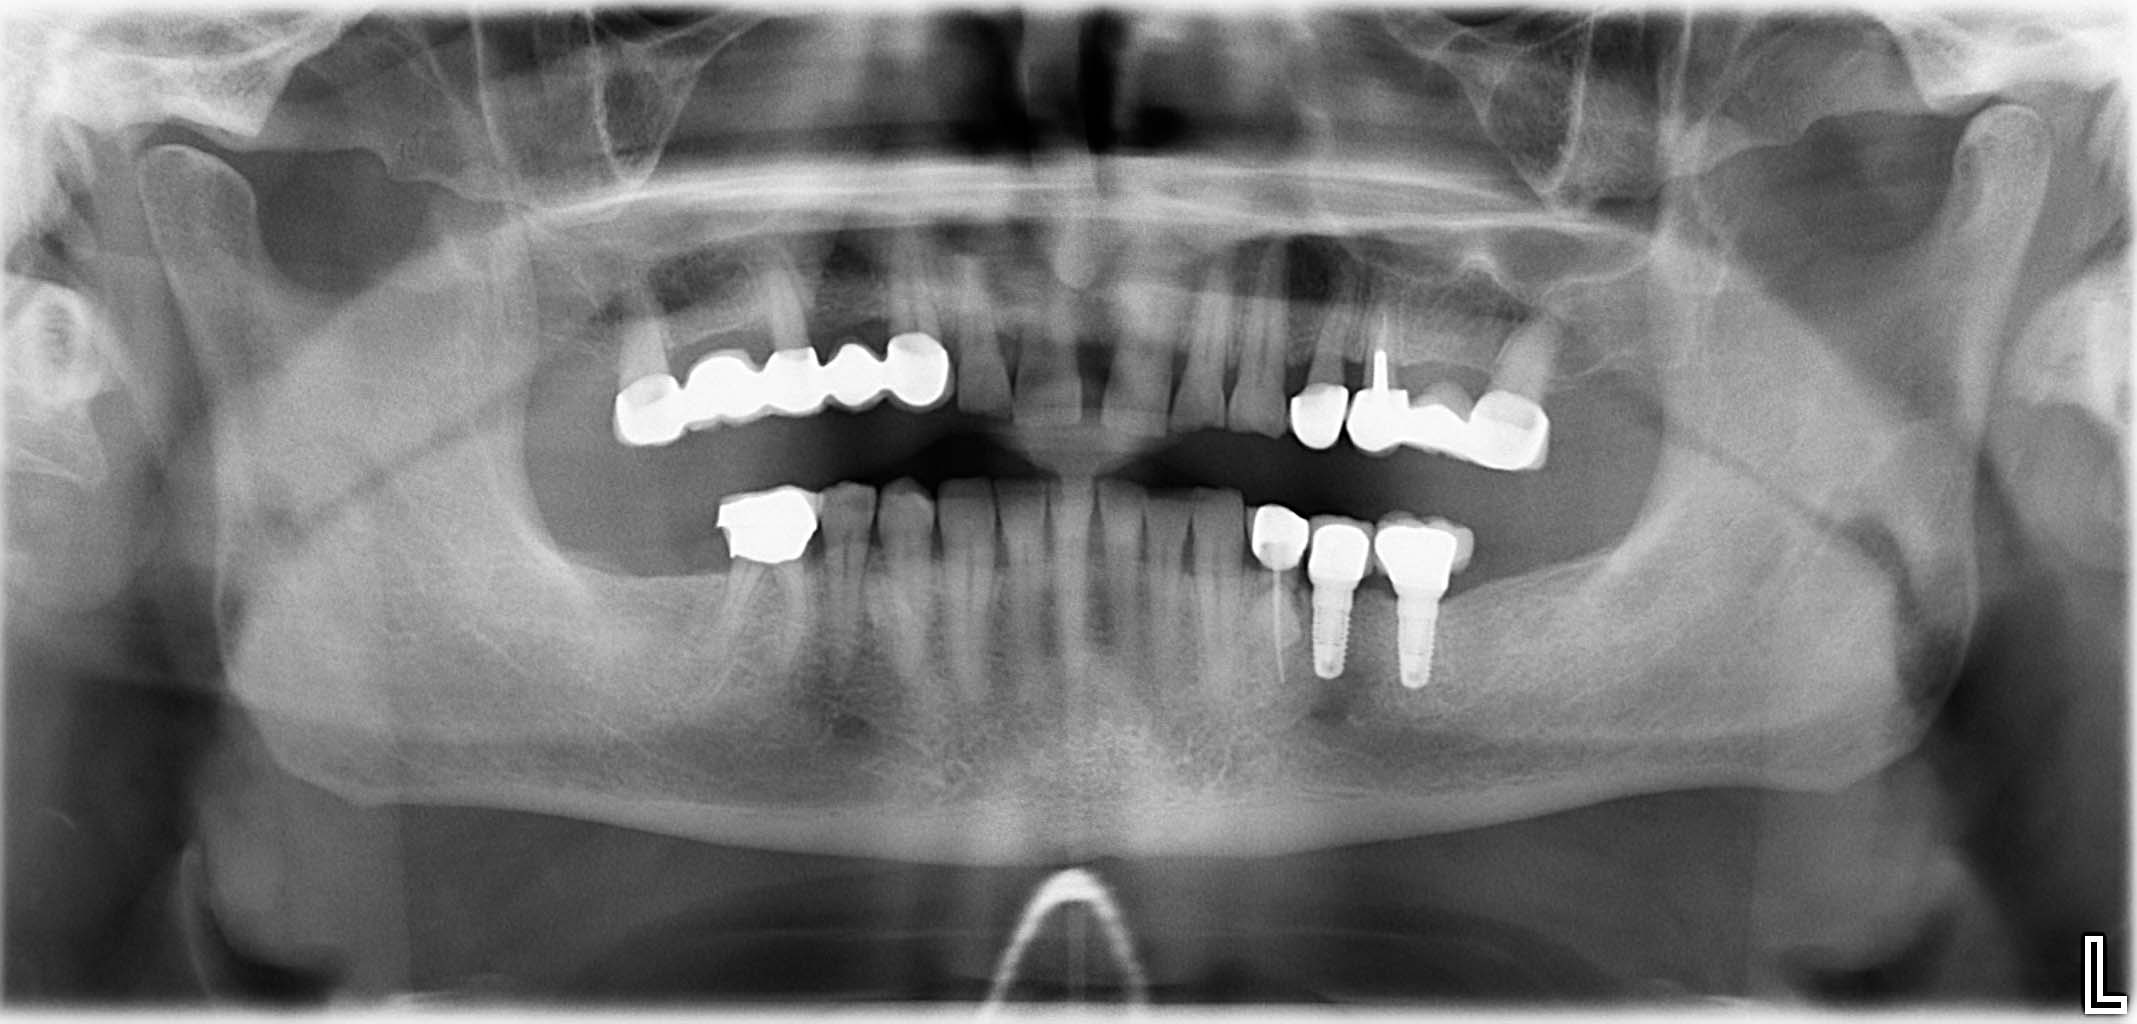

Ausgangssituation: Zahn 36 mit apikaler Beherdung, nicht erhaltungswürdig

Erfolgreich implantierte Patientenfälle (klinische Fotos)